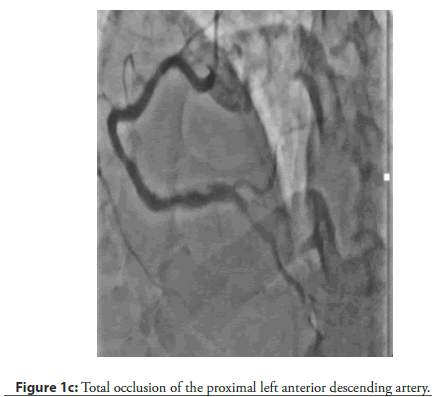

On admission, his blood pressure was 120/80 mmHg, and his heart rate was 72 beats per minute. Electrocardiography (ECG) demonstrated nonspecific ST-T wave changes in leads I, II, III, aVF, and aVL. Laboratory evaluation showed normal cardiac enzyme levels. Transthoracic Echocardiography (TTE) revealed a Left Ventricular Ejection Fraction (LVEF) of 62% without regional wall motion abnormalities. Diagnostic Coronary Angiography (CAG) demonstrated 90% stenosis in the Left Circumflex Artery (LCX) and Obtuse Marginal Branch 2 (OM2), along with total occlusion of the proximal Left Anterior Descending (LAD) artery (Figure 1a–Figure 1c).

The patient and his family declined Coronary Artery Bypass Graft (CABG) surgery; therefore, the primary treatment strategy was to attempt revascularization of the LAD CTO lesion. An antegrade approach was selected, with the right femoral artery used as the primary access route and the right radial artery used for additional support. The initial attempts were made using Fielder XT, Fielder XT-R, and Gaia Next 2 guide wires (Figure 2a–Figure 2c). However, the Caravel microcatheter could not be advanced across the tight lesion. Therefore, predilatation was attempted using a 1.25 × 10 mm balloon followed by a 2 × 12 mm Non-Compliant (NC) balloon. Unfortunately, the wire was found to be in a false tract, which resulted in a Type III LAD perforation with subsequent cardiac tamponade. Emergency pericardiocentesis was performed (Figure 3a, Figure 3b). The LAD perforation was successfully sealed using 2 mm and 3 mm Hilal coils (Figure 4a–Figure 4c).